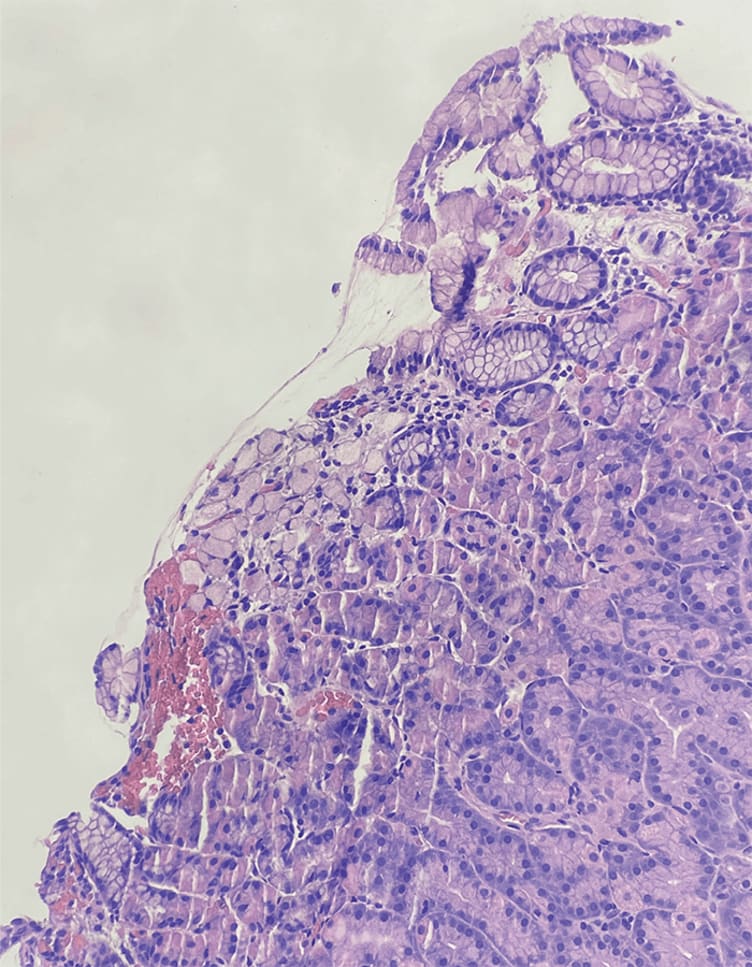

This slide, taken from a prophylactic gastrectomy, shows a small focus of signet-ring cell (poorly cohesive) gastric adenocarcinoma involving the stomach body in a patient with a CDH1 germline mutation. This rare cancer is highly aggressive and its characteristic signet-ring cells feature mucin-filled vacuoles with eccentrically placed nuclei, grow in sheets, can be difficult to identify, and present a challenge for noninvasive diagnostic approaches.